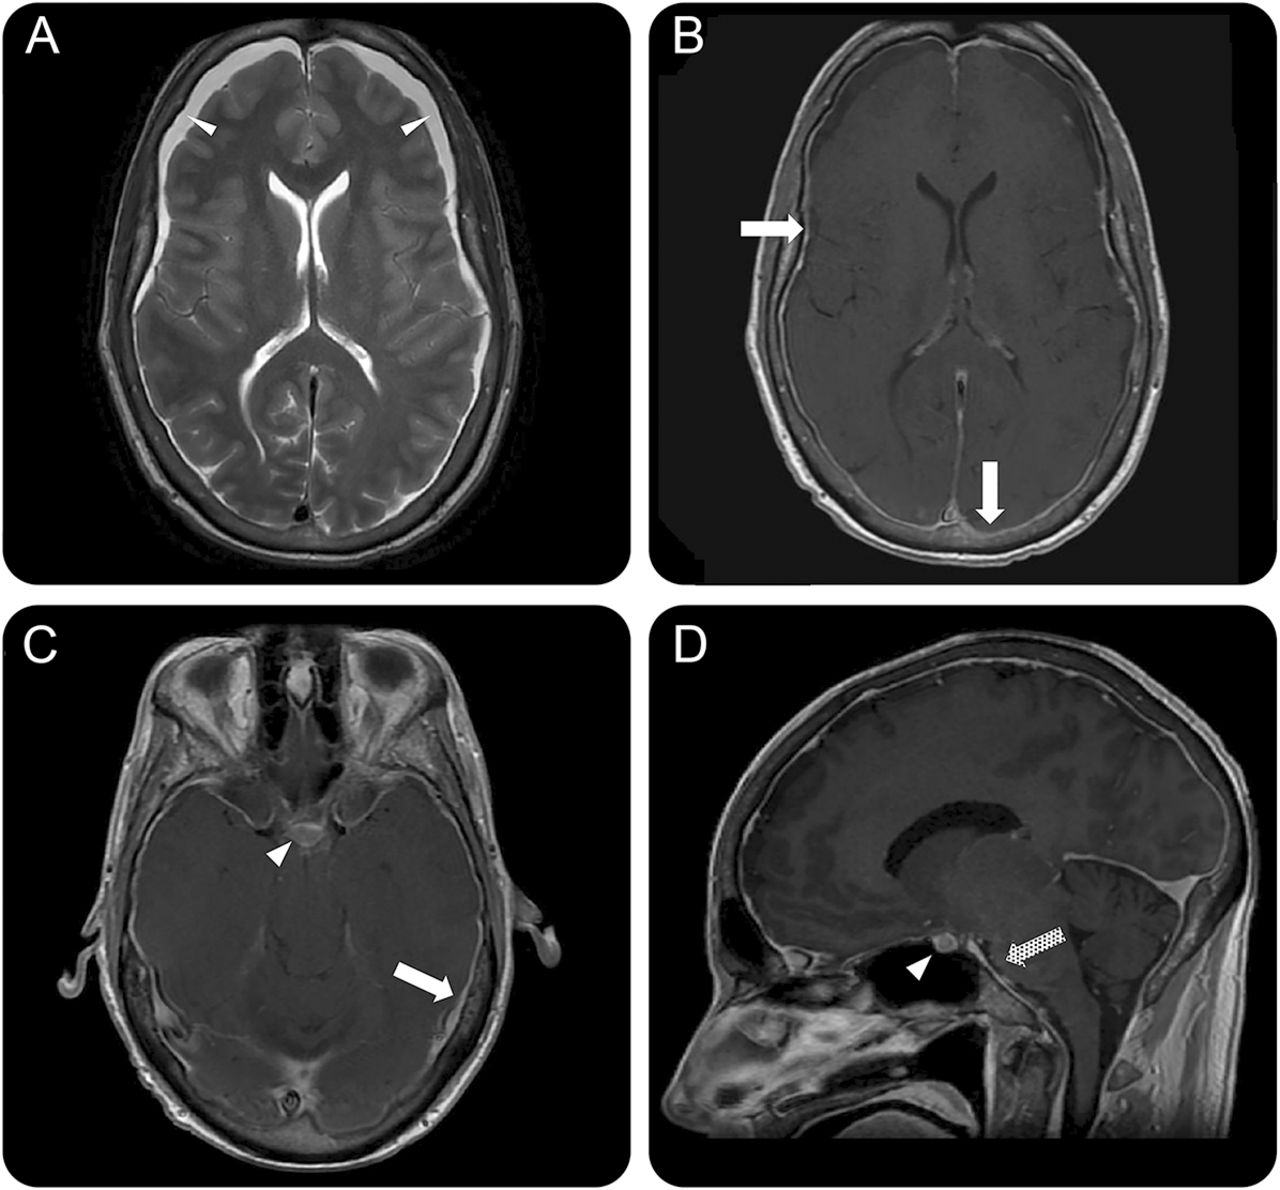

磁共振成像的大脑是通过病人的肿瘤学家,结果提示神经学咨询(首页图)。

(一)轴向t2加权和(B) postcontrast t1影像展示两国硬膜下集合(细的白色箭头)和扩散pachymeningeal增强(白色箭头)。金宝搏188手机app(C)轴向和(D)矢状postcontrast t1加权对比突出垂体充血(白色箭头),pachymeningeal增强(白色箭头),脑干凹陷(网纹箭头)。

磁共振成像的大脑显示弥漫性pachymeningeal增强,双边额硬膜下流体集合,slit-like心室(金宝搏188手机app图中,A和B)、垂体充血(图中,C脑干)和凹陷的抹杀prepontine水箱和减少之间的距离脑桥和mammillary机构(图中,C和D)。

这个病人的MRI显示的所有核磁共振的发现颅内低血压,可想起的记忆中:硬膜下流体集合,增强pachymeninges,充血的静脉结构、垂体充血,大脑的下垂。金宝搏188手机app2认知能力下降和焦颅神经赤字可以开发时减少脑脊液压力导致大脑松弛和脑干。3